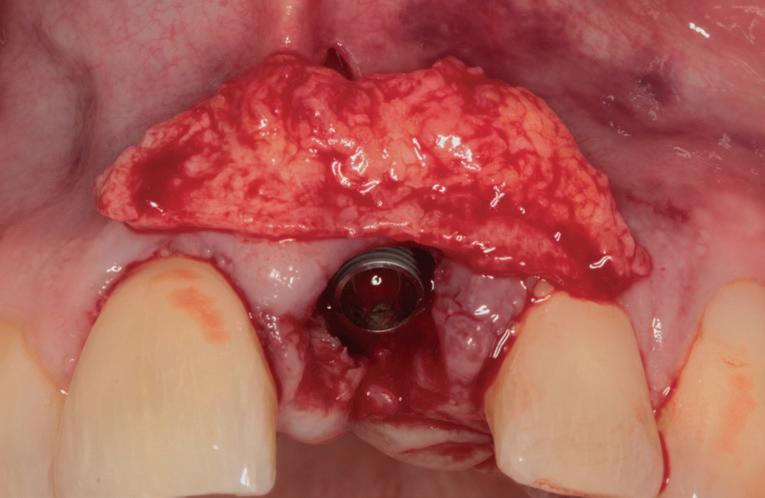

SITE AUGMENTATION Reconstituirea țesutului moale periimplantar și papilar în zona estetică

RECONSTITUIREA țesuturilor moi periimplantare. Scopul acestui raport de caz este de a demonstra procedurile chirurgicale utilizate pentru corectarea unui defect al țesuturilor moi periimplantare folosind țesutul moale interdentar în combinație cu tuberozitatea ca locație donatoare de țesut conjunctiv, utilizând o abordare prin tunelizare într-o zonă estetică.